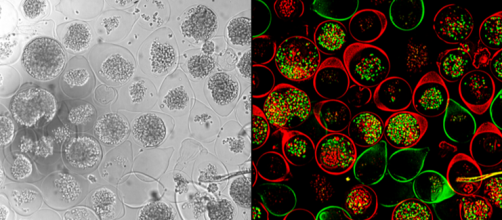

Des immunothérapies efficaces contre les cancers colorectaux